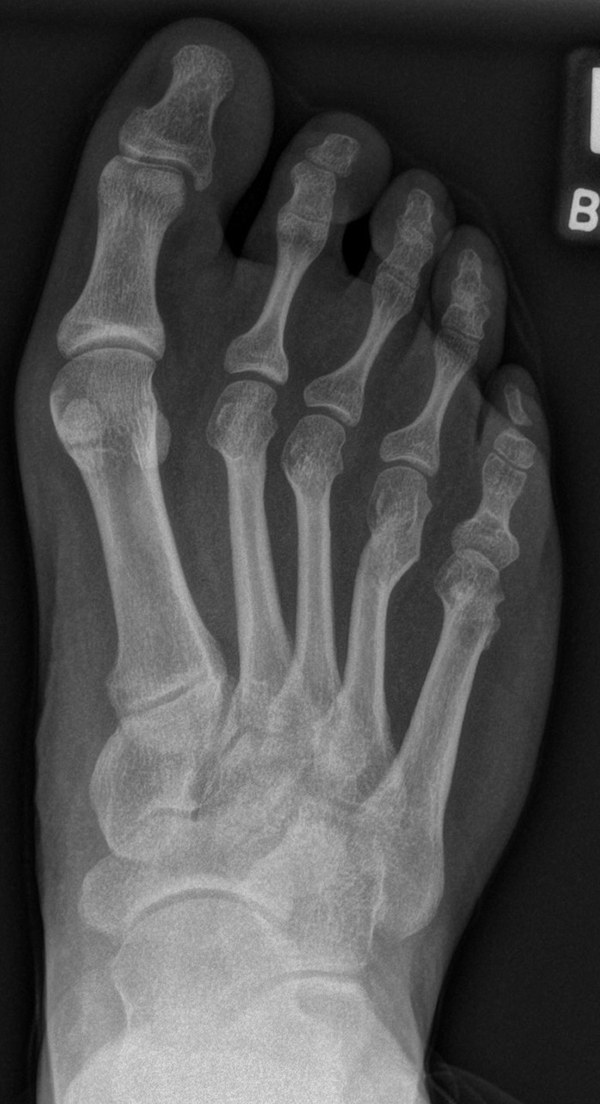

In der Regel bestehen aktive Wachstumsfugen bei Mädchen bis zum 12. und bei Jungen bis zum 14. Lebensjahr, mit Abweichungen von einem Jahr nach unten und nach oben. Präzise Informationen unter anderem darüber gibt das präoperative Röntgenbild (Abb. 2).

Abb. 2 a-c: offene Wachstumsfugen MT I Basis und Zehen (a), teilweise geöffnete Wachstumsfugen (b) und geschlossene Wachstumsfugen (c).